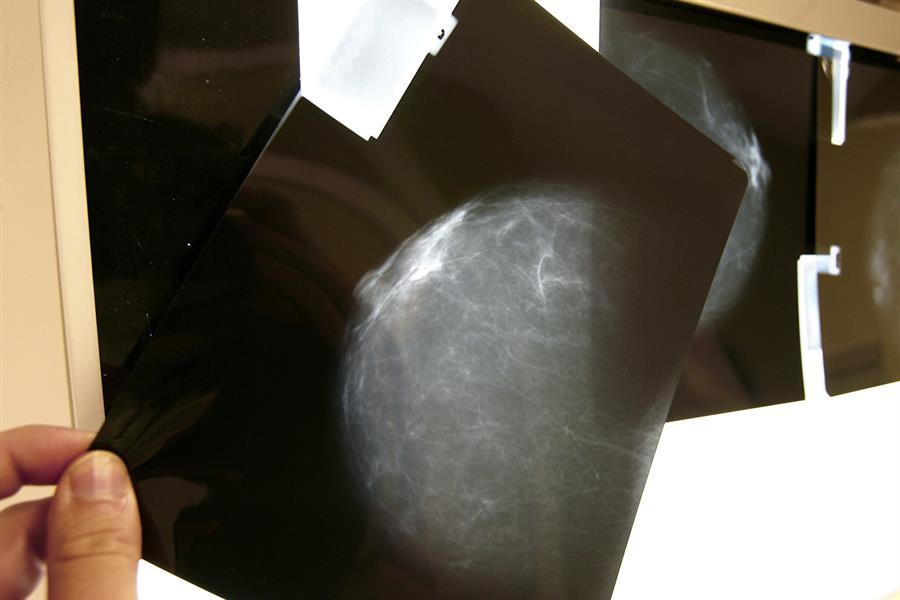

Un grupo de investigadores del Hospital del Mar de Barcelona (España) ha estudiado las mamografías de 629.000 mujeres de España para ver qué tipos de tumores benignos de mama tienen más probabilidad de convertirse en cancerígenos.

Los investigadores han analizado los datos de 629.087 mujeres a las que se realizaron 2.327.384 mamografías entre 1995 y 2015, y las siguieron hasta el año 2017.